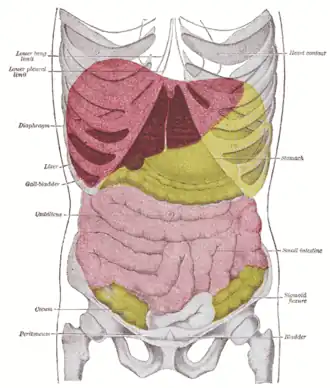

Topography of thoracic and abdominal viscera

Topography of thoracic and abdominal viscera -